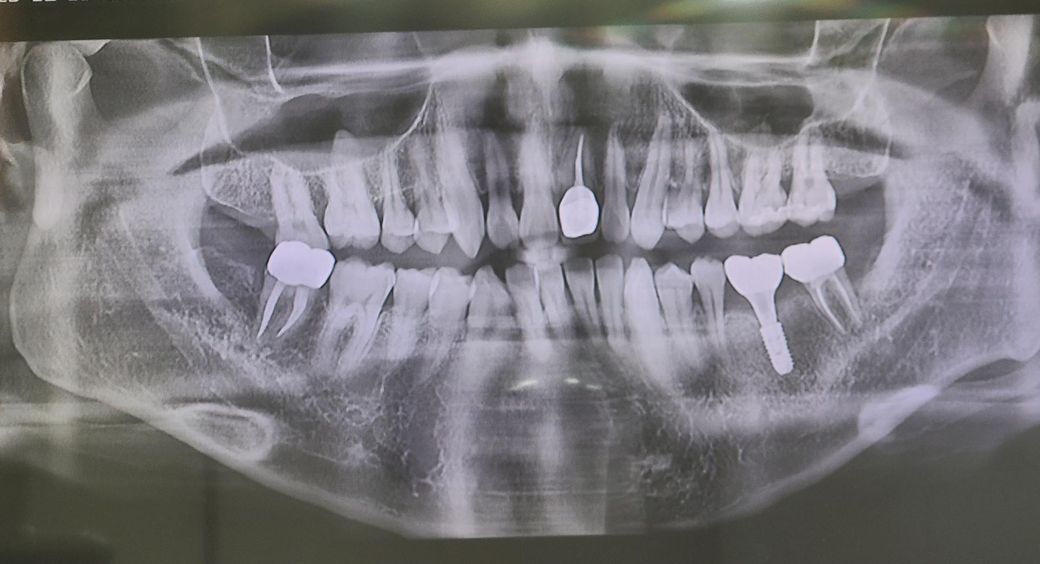

오른쪽 맨끝 어금니 입니다. 10년된 신경치료한 금크라운을 지르코니아로 새로 교체한지 2개월 됬는데요. 저 동그라미친 부분 잇몸이 누르면 아프고 자주 간질거립니다. 물론 저번주에 잇몸치료도 받고왔습니다. 근데 다시그러네요. 받을때만 괜찮습니다. 이러면 크라운경계부 문제인가요? 아니면 뿌리문제일까요. 최근에 찍은 엑스레이도 첨부합니다. 크라운문제라면 A/S가능한지 궁금합니다.

• 1번 째 사진